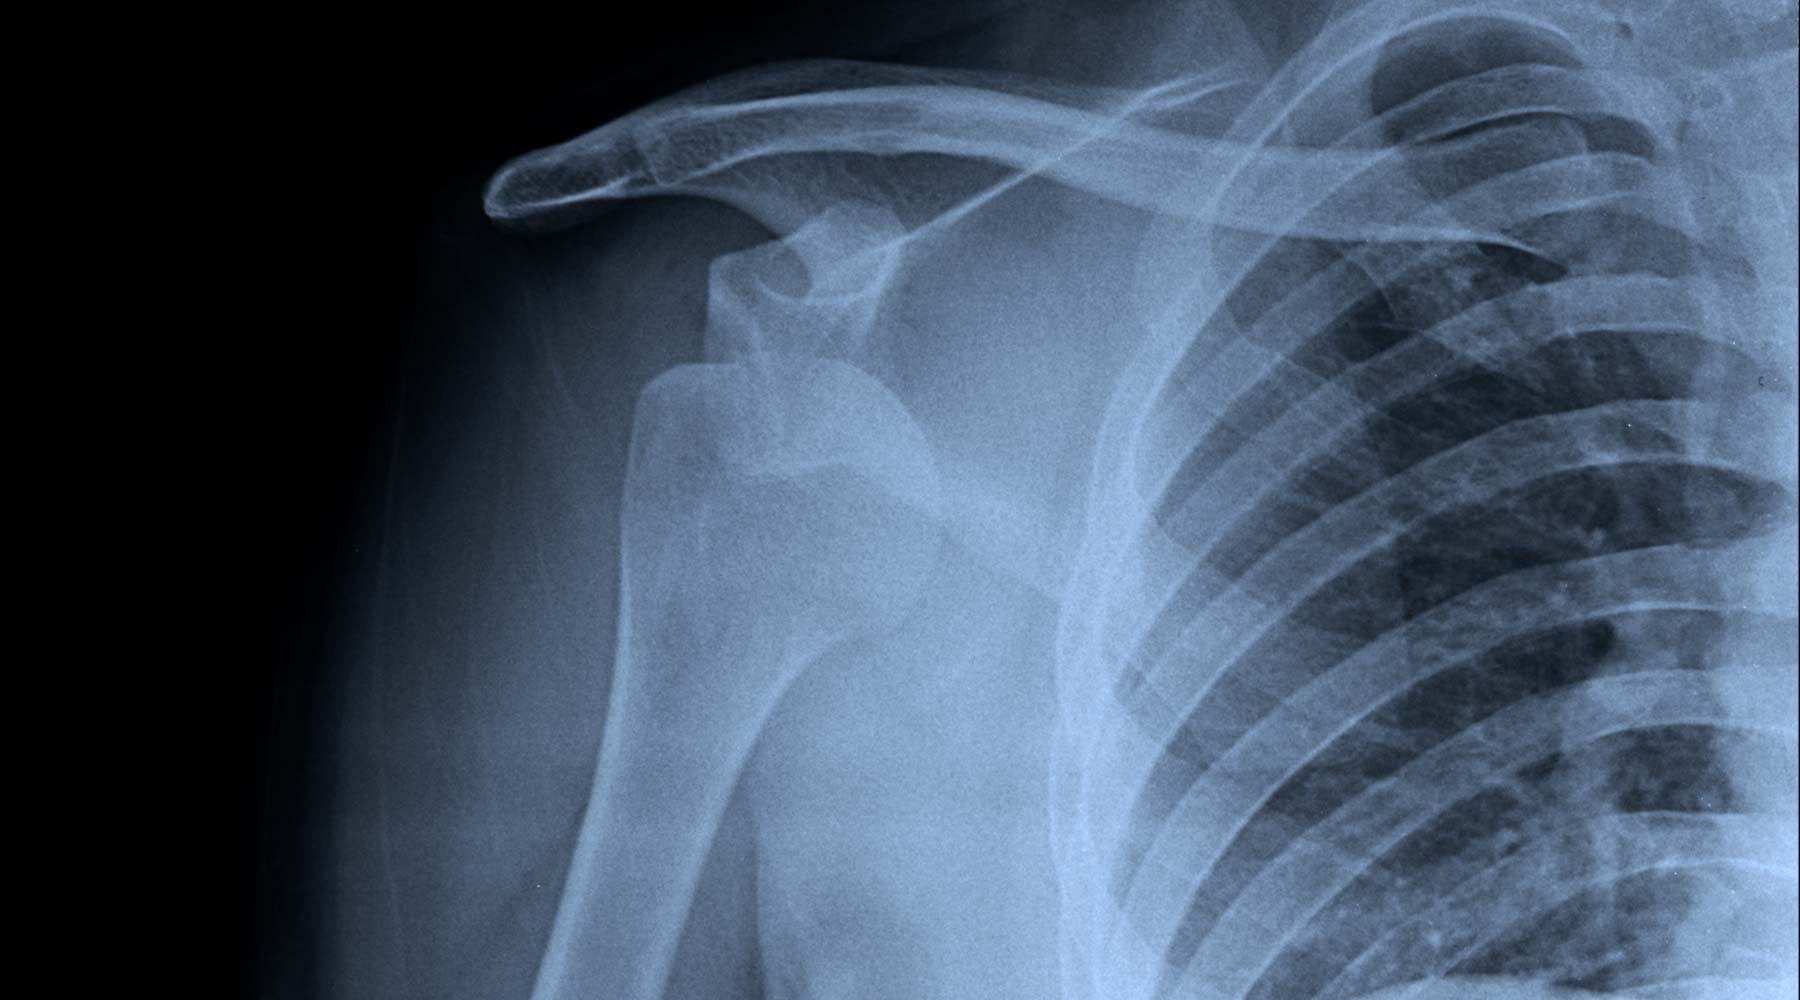

Anterior dislocation of the right shoulder. It's a classic mountain biking injury, and I guess it's one that plenty of people reading this have been through themselves. The first is always the worst, and I wish I had a rock & roll story about landing a 60ft gap to flat, but I haven't. Actually I did it half drunk at my wife's birthday party when the inevitable mucking-about-on-bikes kicked in (I was on a hot lap and would clearly have won if someone hadn't put that tree in the way). I was younger than I am now, so didn't do the recovery like I should have, and just carried on riding bikes. A few dislocations later and now it just pops out for the stupidest of reasons. Last time it was the night before the 'Ard Rock Enduro, and I didn't get to race. Time to get it sorted.

I'm going in for a surgery next week. An Arthroscopic Bankart Repair, to give it it's full name. Basically they're going to pin the glenoid ligament back into place using what appears to be a only-slightly modified rawl-plug. Yes, there is a hammer and a power drill involved. But I'm assured it will all be fine and the good news is, I'll be under general anaesthetic so I won't have any idea what the dude with the drill is up to. The bad news is that I'll be out of action for some time - and that's likely to affect how I'm able to run Airdrop Bikes.